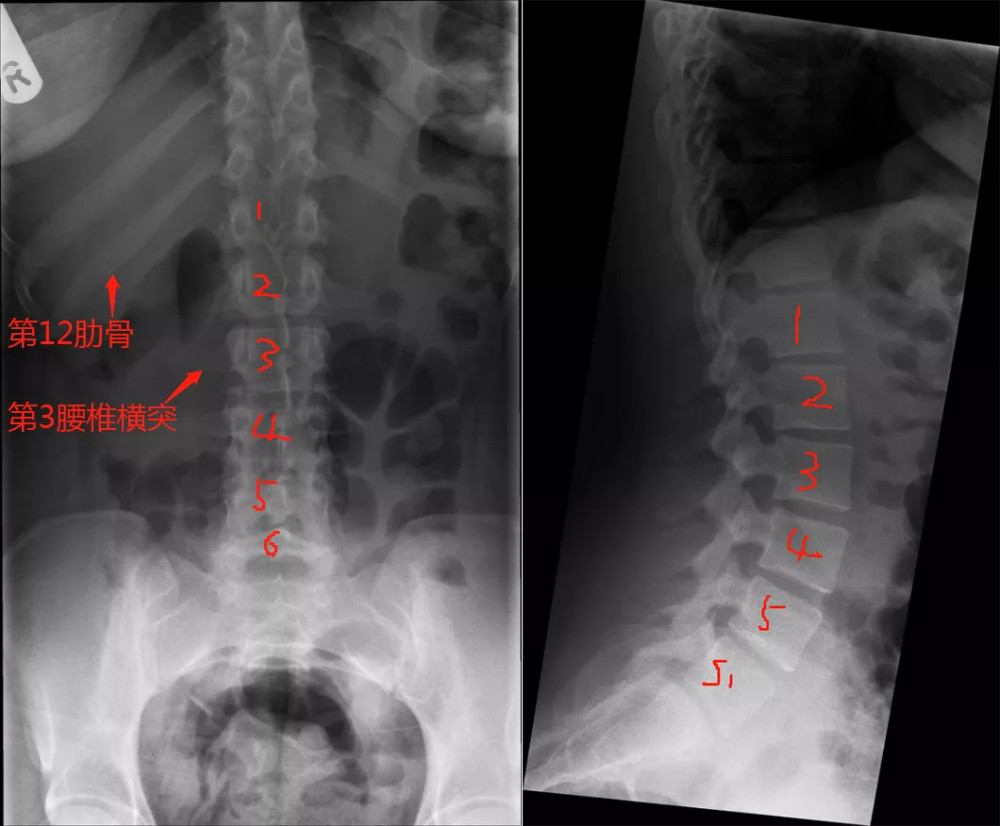

文章插图

图解

此病例为骶椎腰化